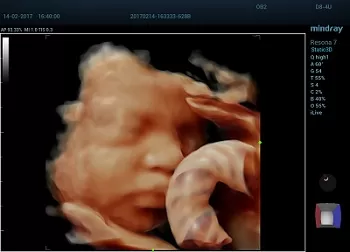

O νέος premium υπερηχογράφος Resona του κατασκευαστικού οίκου Mindray:

Mια νέα επαναστατική πλατφόρμα με την μοναδική τεχνολογία zone sonography technology ZST+ η οποία προσφέρει δεκαπλάσια ταχύτητα σάρωσης.

Οι καινοτόμες τεχνολογίες:

- Dynamic focusing

- HD Scope

- Sound Speed Compensation

- Sound Touch Elastography

- Total Recall Imaging

- Advanced Accoustic Acquisition

- Channel Data Processing

το καθιστούν ένα μοναδικό διαγνωστικό εργαλείο στις υπηρεσίες του ασθενούς.